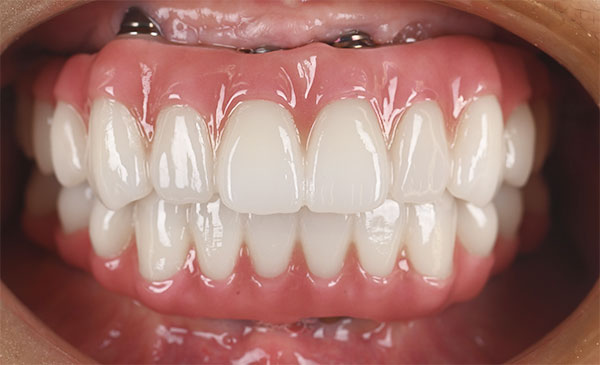

前方のインプラントは残し、他院埋入のザイゴマインプラントを除去し、同時に新しいザイゴマインプラントを適切な位置に再埋入を行っております。治療後数年経過しておりますが良好な状態を保っております。

術後の正面観とスマイル時

| 治療期間 | 6ヶ月〜1年 |

| 治療方法 | 左右ザイゴマインプラント除去及び再埋入・上下仮歯(2回)及びフルジルコニア最終補綴物 |

7,040,000円(税込) ※再手術費用・上下仮歯2回(1,540,000円)、及びフルジルコニア最終補綴物(5,500,000円) |